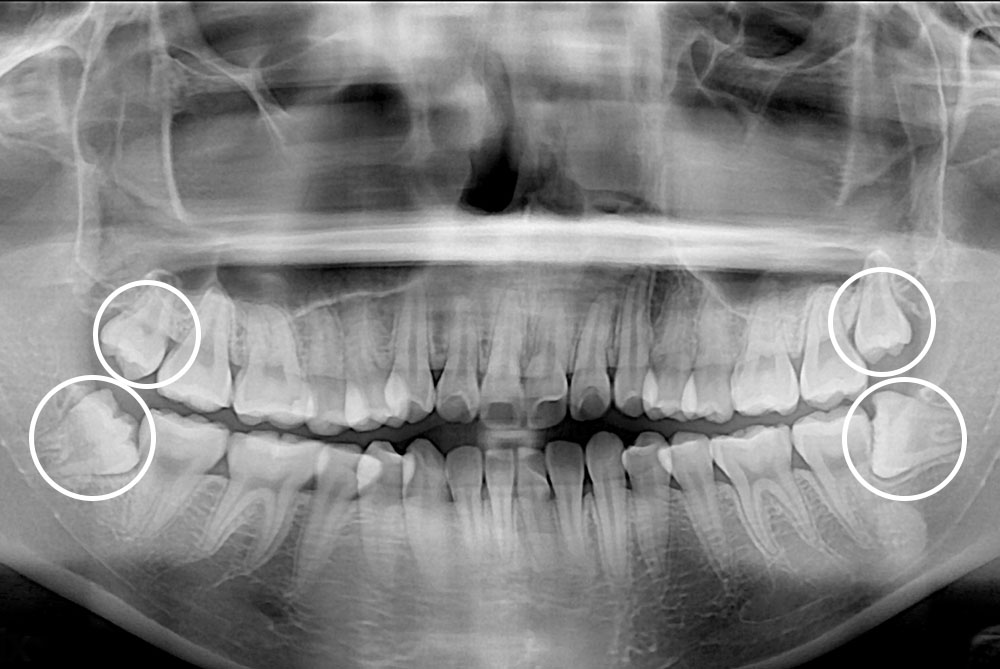

[사랑니] 매복 사랑니 발치

치료후 : 2019-09-11